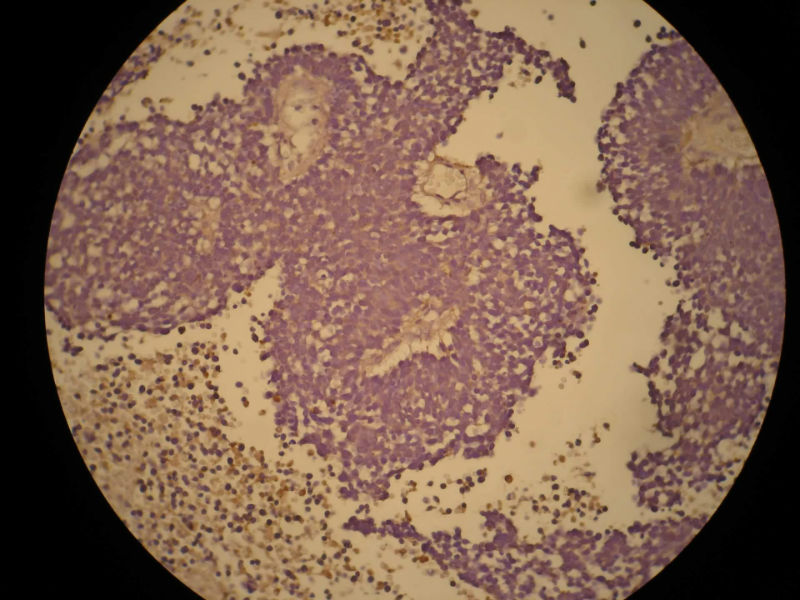

患者,M50Y,左侧肢体乏力半个月,肌力2级

MRI示右顶叶和小脑占位性病变,增强强化明显

术中见鱼肉样质脆,血管丰富,边界不清,部分囊性变,分块切除

大体:碎组织,4.2*3.5*2cm,呈鱼肉状,质嫩软。其间可见少量灰白组织,质韧。

Based on histology and immunohistochemistry, metastatic neuroendocrine carcinoma needs to be ruled out. I suggest TTF-1 stain. Also pay attention to nuclear morphology at high power view and see if it fits small cell carcinoma. It doesn't have to be a primary CNS tumor just because the border appears infiltrative.

谢谢Dr.mjma和楼上各位的指导。形态学符合小细胞癌。我们加做TTF-1,CD56和NSE,下周有结果。